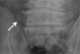

Short rib syndrome type 3

Short rib–polydactyly syndrome is a family of four closely related dysplasias: [Source: Wikipedia ]